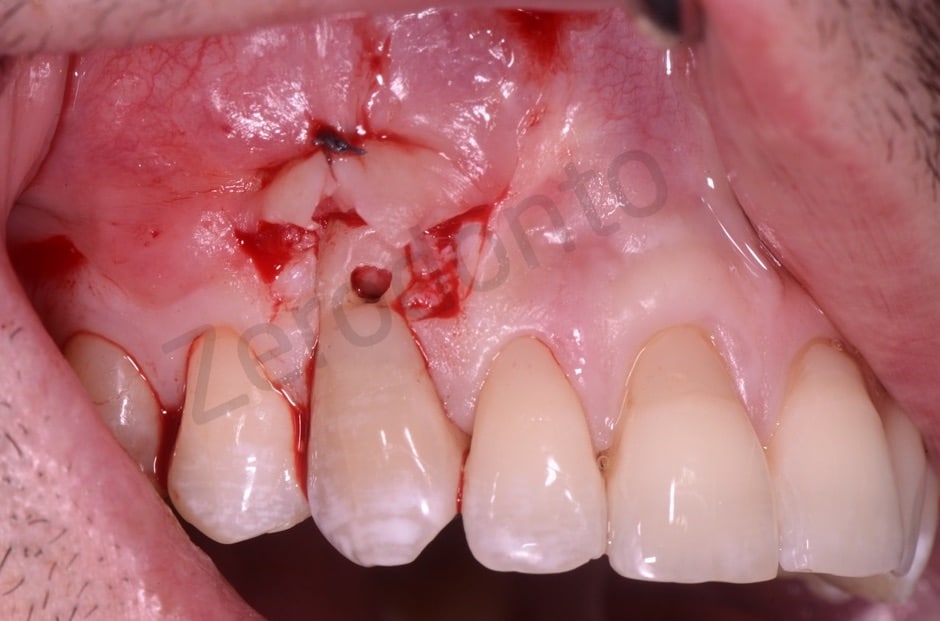

A coronal repositioning flap first at partial thickness then total thickness and finally a periosteal incision to mobilize the flap were performed. The anatomical papillae were disepithelized to allow the sliding of the surgical papillae.

After removing the granulation tissue as far as possible compatibly with maintaining the vitality of the tooth, the cavity was filled with Biodentine, a bioceramic, perfectly biocompatible cement based on synthetic tricalcium silicate which is a valid substitute for dentine itself. The control is at one year.

The lesion

Detail of the lesion